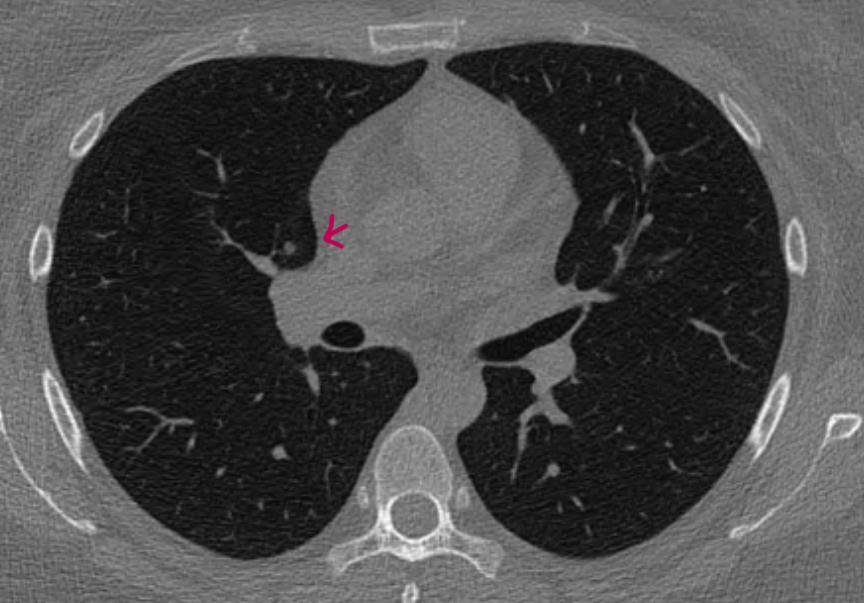

• 2번 째 사진

• 제시된 CT 단면만으로 확정적인 결론을 내리기는 어렵지만, 영상 형태를 종합하면 전형적인 고형 결절로 보기는 제한이 있습니다. 표시된 병변은 경계가 비교적 또렷한 구조처럼 보이지만, 연속된 슬라이스에서 일정한 덩어리로 유지되는 고형 결절의 특징보다는 인접 구조와 이어지는 양상이 의심됩니다. 특히 슬라이스 두께가 1mm와 3mm에서 다르게 보이고 특정 시리즈에서만 강조되는 점은 부분용적 효과에 의해 고형처럼 보일 가능성을 시사합니다.

간유리 결절은 폐 실질 내에서 흐릿하게 음영이 증가하면서 혈관 구조가 그대로 비쳐 보이는 형태가 특징인데, 현재 영상에서는 그러한 전형적인 간유리 음영보다는 비교적 명확한 구조물 형태로 관찰됩니다. 따라서 간유리 결절로 단정하기도 어렵고, 고형 결절로 보기에도 일관성이 부족한 상태입니다.

오히려 폐혈관이 단면으로 보이거나 혈관과 연속된 구조일 가능성이 더 높습니다. 폐 CT에서는 혈관이 단면에서 원형 또는 타원형으로 보일 수 있고, 촬영 각도나 절편 두께에 따라 결절처럼 오인되는 경우가 흔합니다. 동일 위치에서 1년 전과 이후 CT에서 반복적으로 보이는 경우도 정상 혈관 구조로 설명이 가능합니다.

결론적으로 현재 자료만으로는 고형 결절로 확정하기 어렵고, 간유리 결절의 전형적 소견도 아니며, 혈관 또는 혈관 관련 구조일 가능성이 상대적으로 높습니다. 최종 판단은 1mm 이하 얇은 절편의 연속 영상에서 병변이 독립된 결절 형태로 유지되는지, 혈관과 연결되는지를 확인하는 것이 핵심이며 동일 조건의 CT로 비교 판독을 받는 것이 가장 정확합니다.